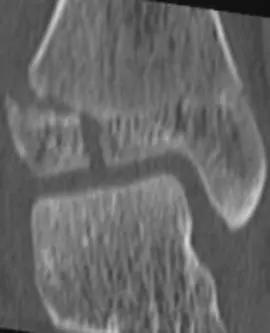

38种特殊骨折经典影像,你见过多少?

骨折